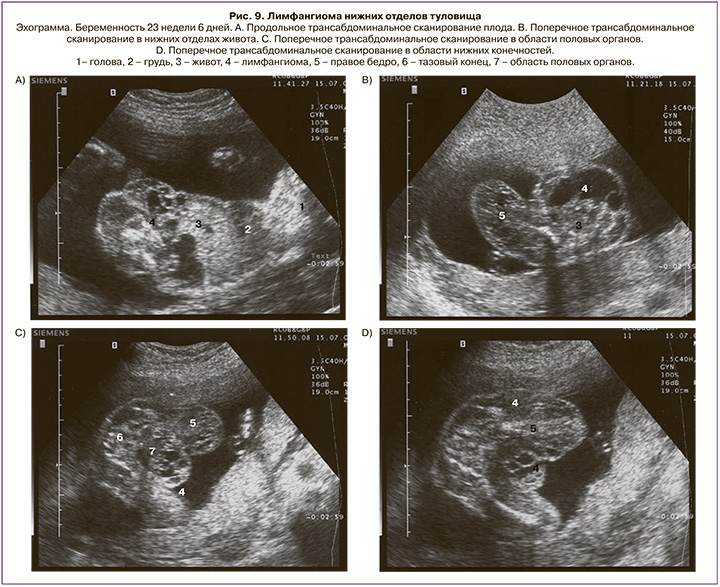

Лимфангиома бедра и голени выявлена у 5 плодов (9,3%) в сроках от 21 до 34 недель. Беременность завершилась срочными родами в 4 наблюдениях. Прерывание беременности выполнено в одном случае при сроке 22 недели беременности (лимфангиома занимала нижние отделы живота и малого таза, распространялась на промежность, половые органы и правое бедро, ее диаметр составил 6,3 см) (рис. 9).